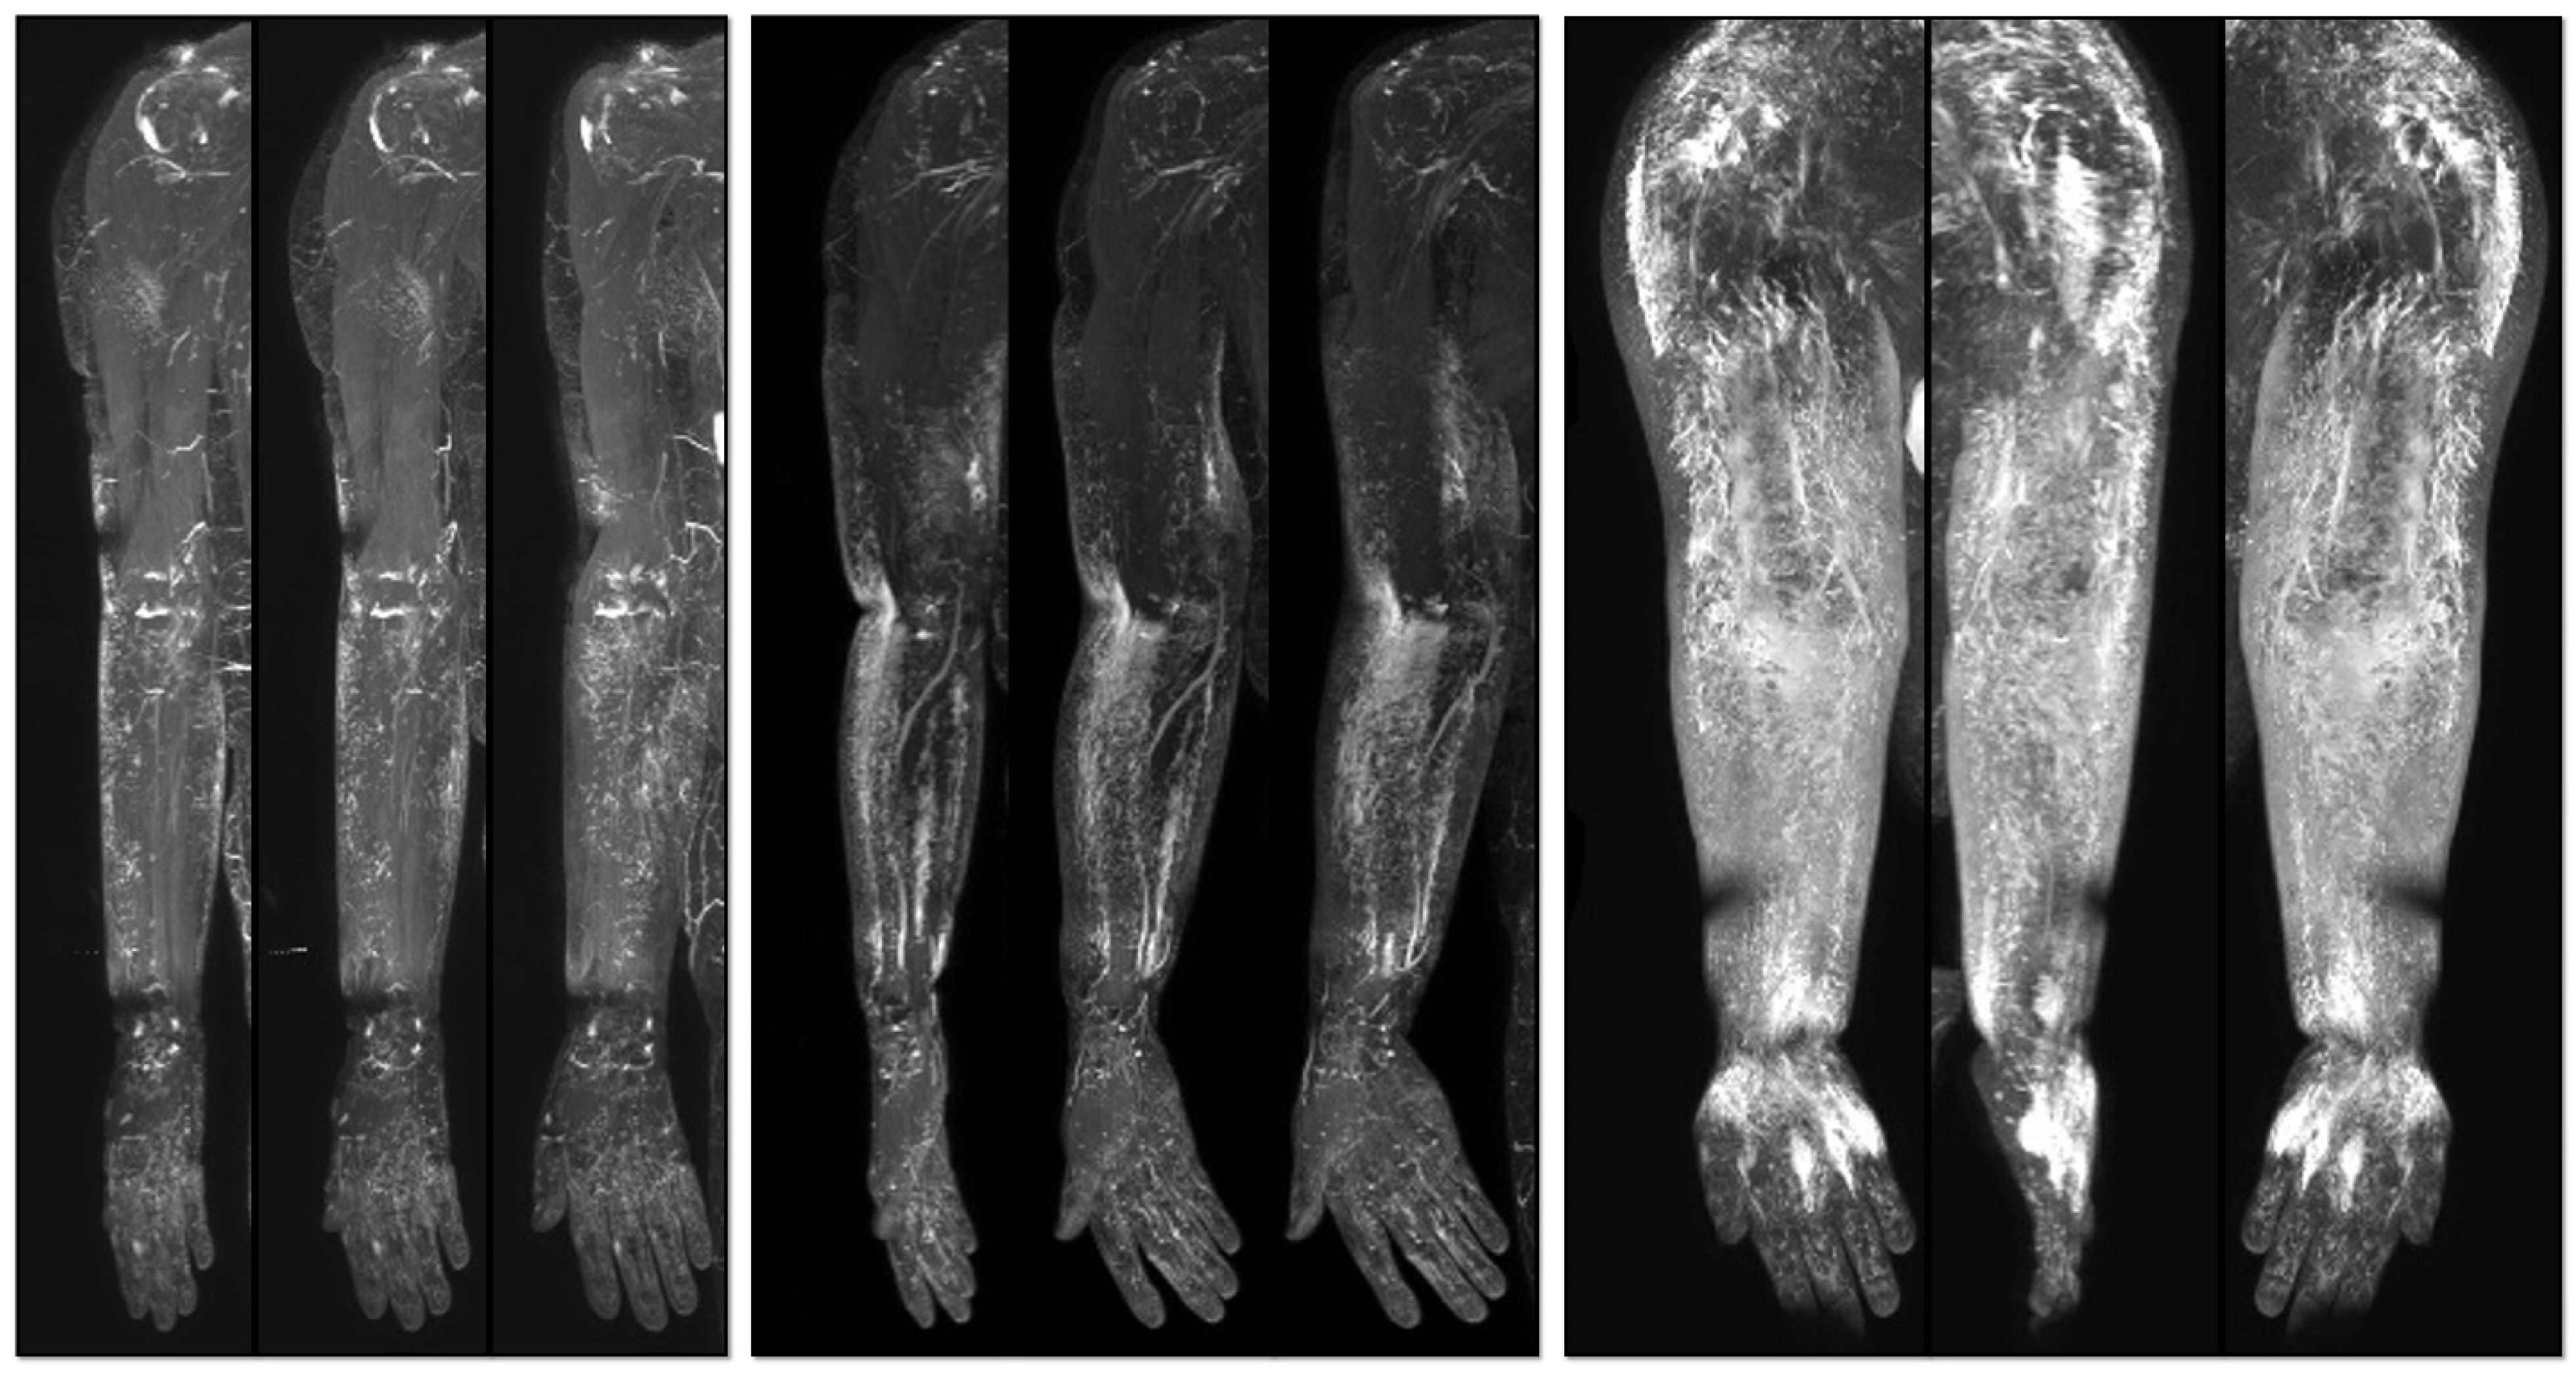

Utilization of Noncontrast Magnetic Resonance Lymphangiography for Selection of Effective Surgical Method in Breast Cancer-Related Lymphedema

- Myung, Y.; Park, S.; Kim, B.R.; Yang, E.J.; Park, J.K.-H.; Kang, Y. Validation of a Lymphedema Index Score Based on Noncontrast Magnetic Resonance Lymphangiography: Correlation with Clinical Staging and Indocyanine Green Lymphangiography. Lymphat. Res. Biol. 2023, 21, 70–77. [Google Scholar] [CrossRef] [PubMed]